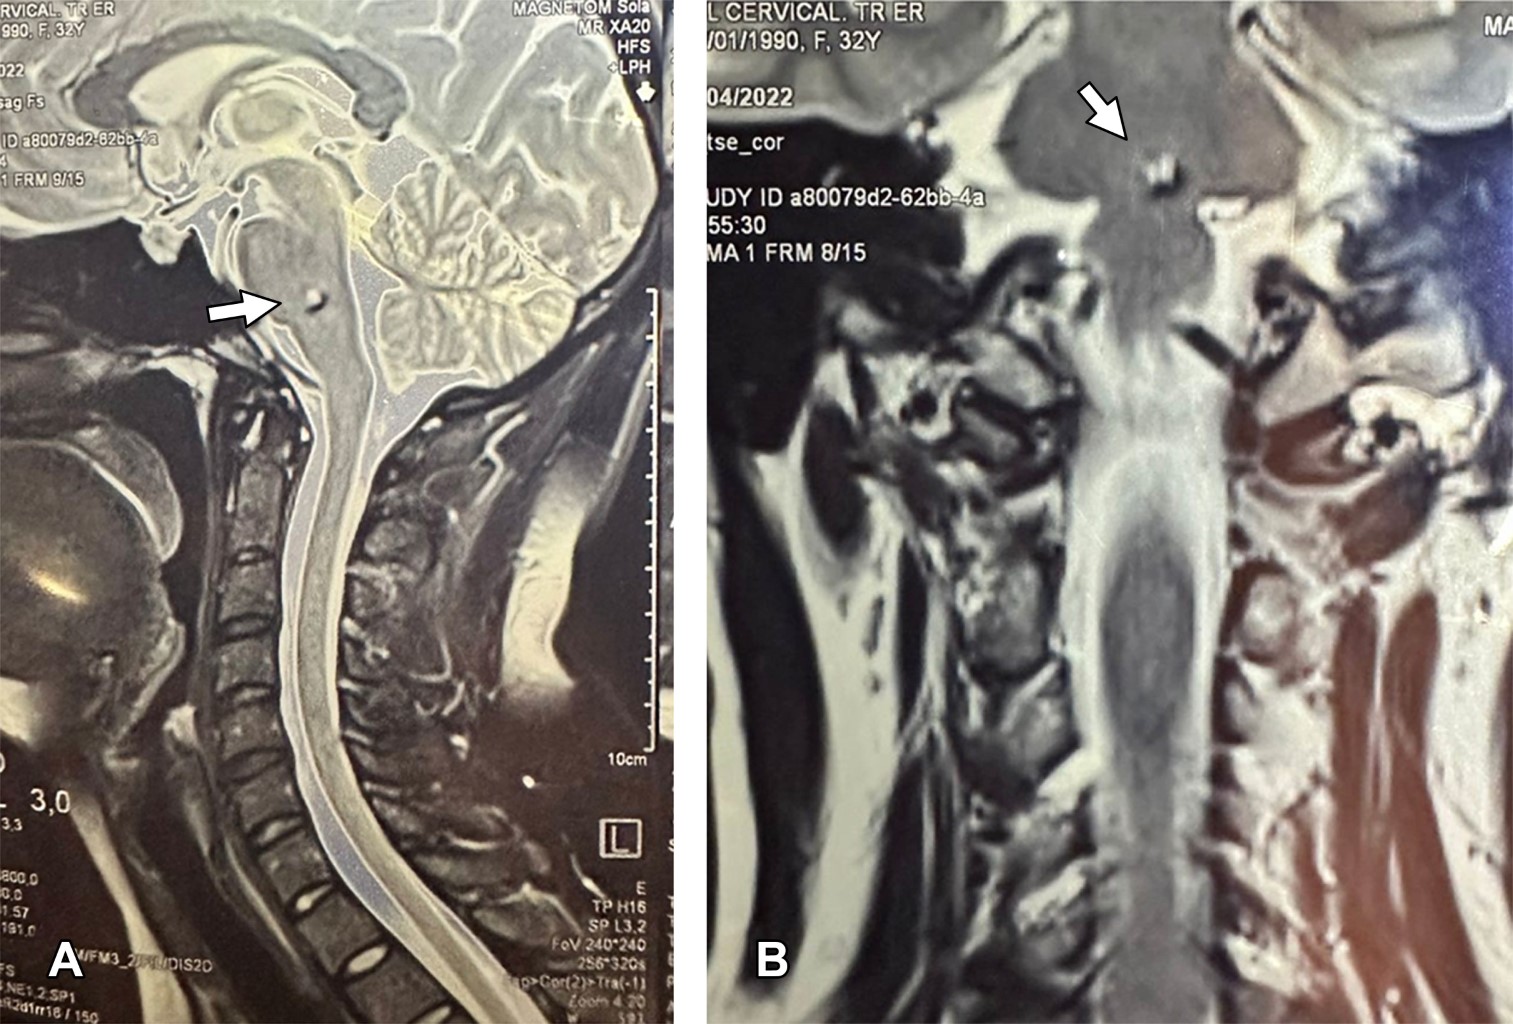

Femenino de 37 años que acudió por cervicalgia, se efectuó resonancia magnética cervical encontrando incidentalmente cavernoma asintomático en protuberancia (Figura 1); dos años después presentó sangrado del mismo (Figura 2), lo cual ocasionó termoanalgesia facial bilateral y del hemitórax derecho, parálisis ipsilateral de maseteros, ataxia, temblor y hemiparesia contralateral (síndrome de Grenet). Las malformaciones venosas cavernosas (MVC) cerebrales son denominadas actualmente "malformaciones venosas de flujo lento". Es la tercera malformación vascular cerebral más común, supratentoriales en ~80% de los casos. Las MVC del tronco encefálico son poco comunes (8 a 22%), de todos los cavernomas intracraneales 40% son hallazgos incidentales; su sintomatología en caso de sangrado es entre los 30 y 60 años, habitualmente son lesiones únicas. La mayoría permanecen asintomáticas. La presentación por hemorragia puede provocar cefalea, convulsiones o déficit neurológico focal. El riesgo de hemorragia es < 0.1 a 1% por paciente-año y de 5% en el tronco encefálico. Se componen de capilares hialinizados, dilatados, de paredes delgadas, rodeados de hemosiderina. La resonancia magnética es de elección diagnóstica, mostrando una apariencia característica de "palomitas de maíz" o "bayas" con pérdida del borde debido a hemosiderina. Las lesiones sintomáticas deben, cuando sea posible, resecarse y la resección completa es curativa.

Figura 1